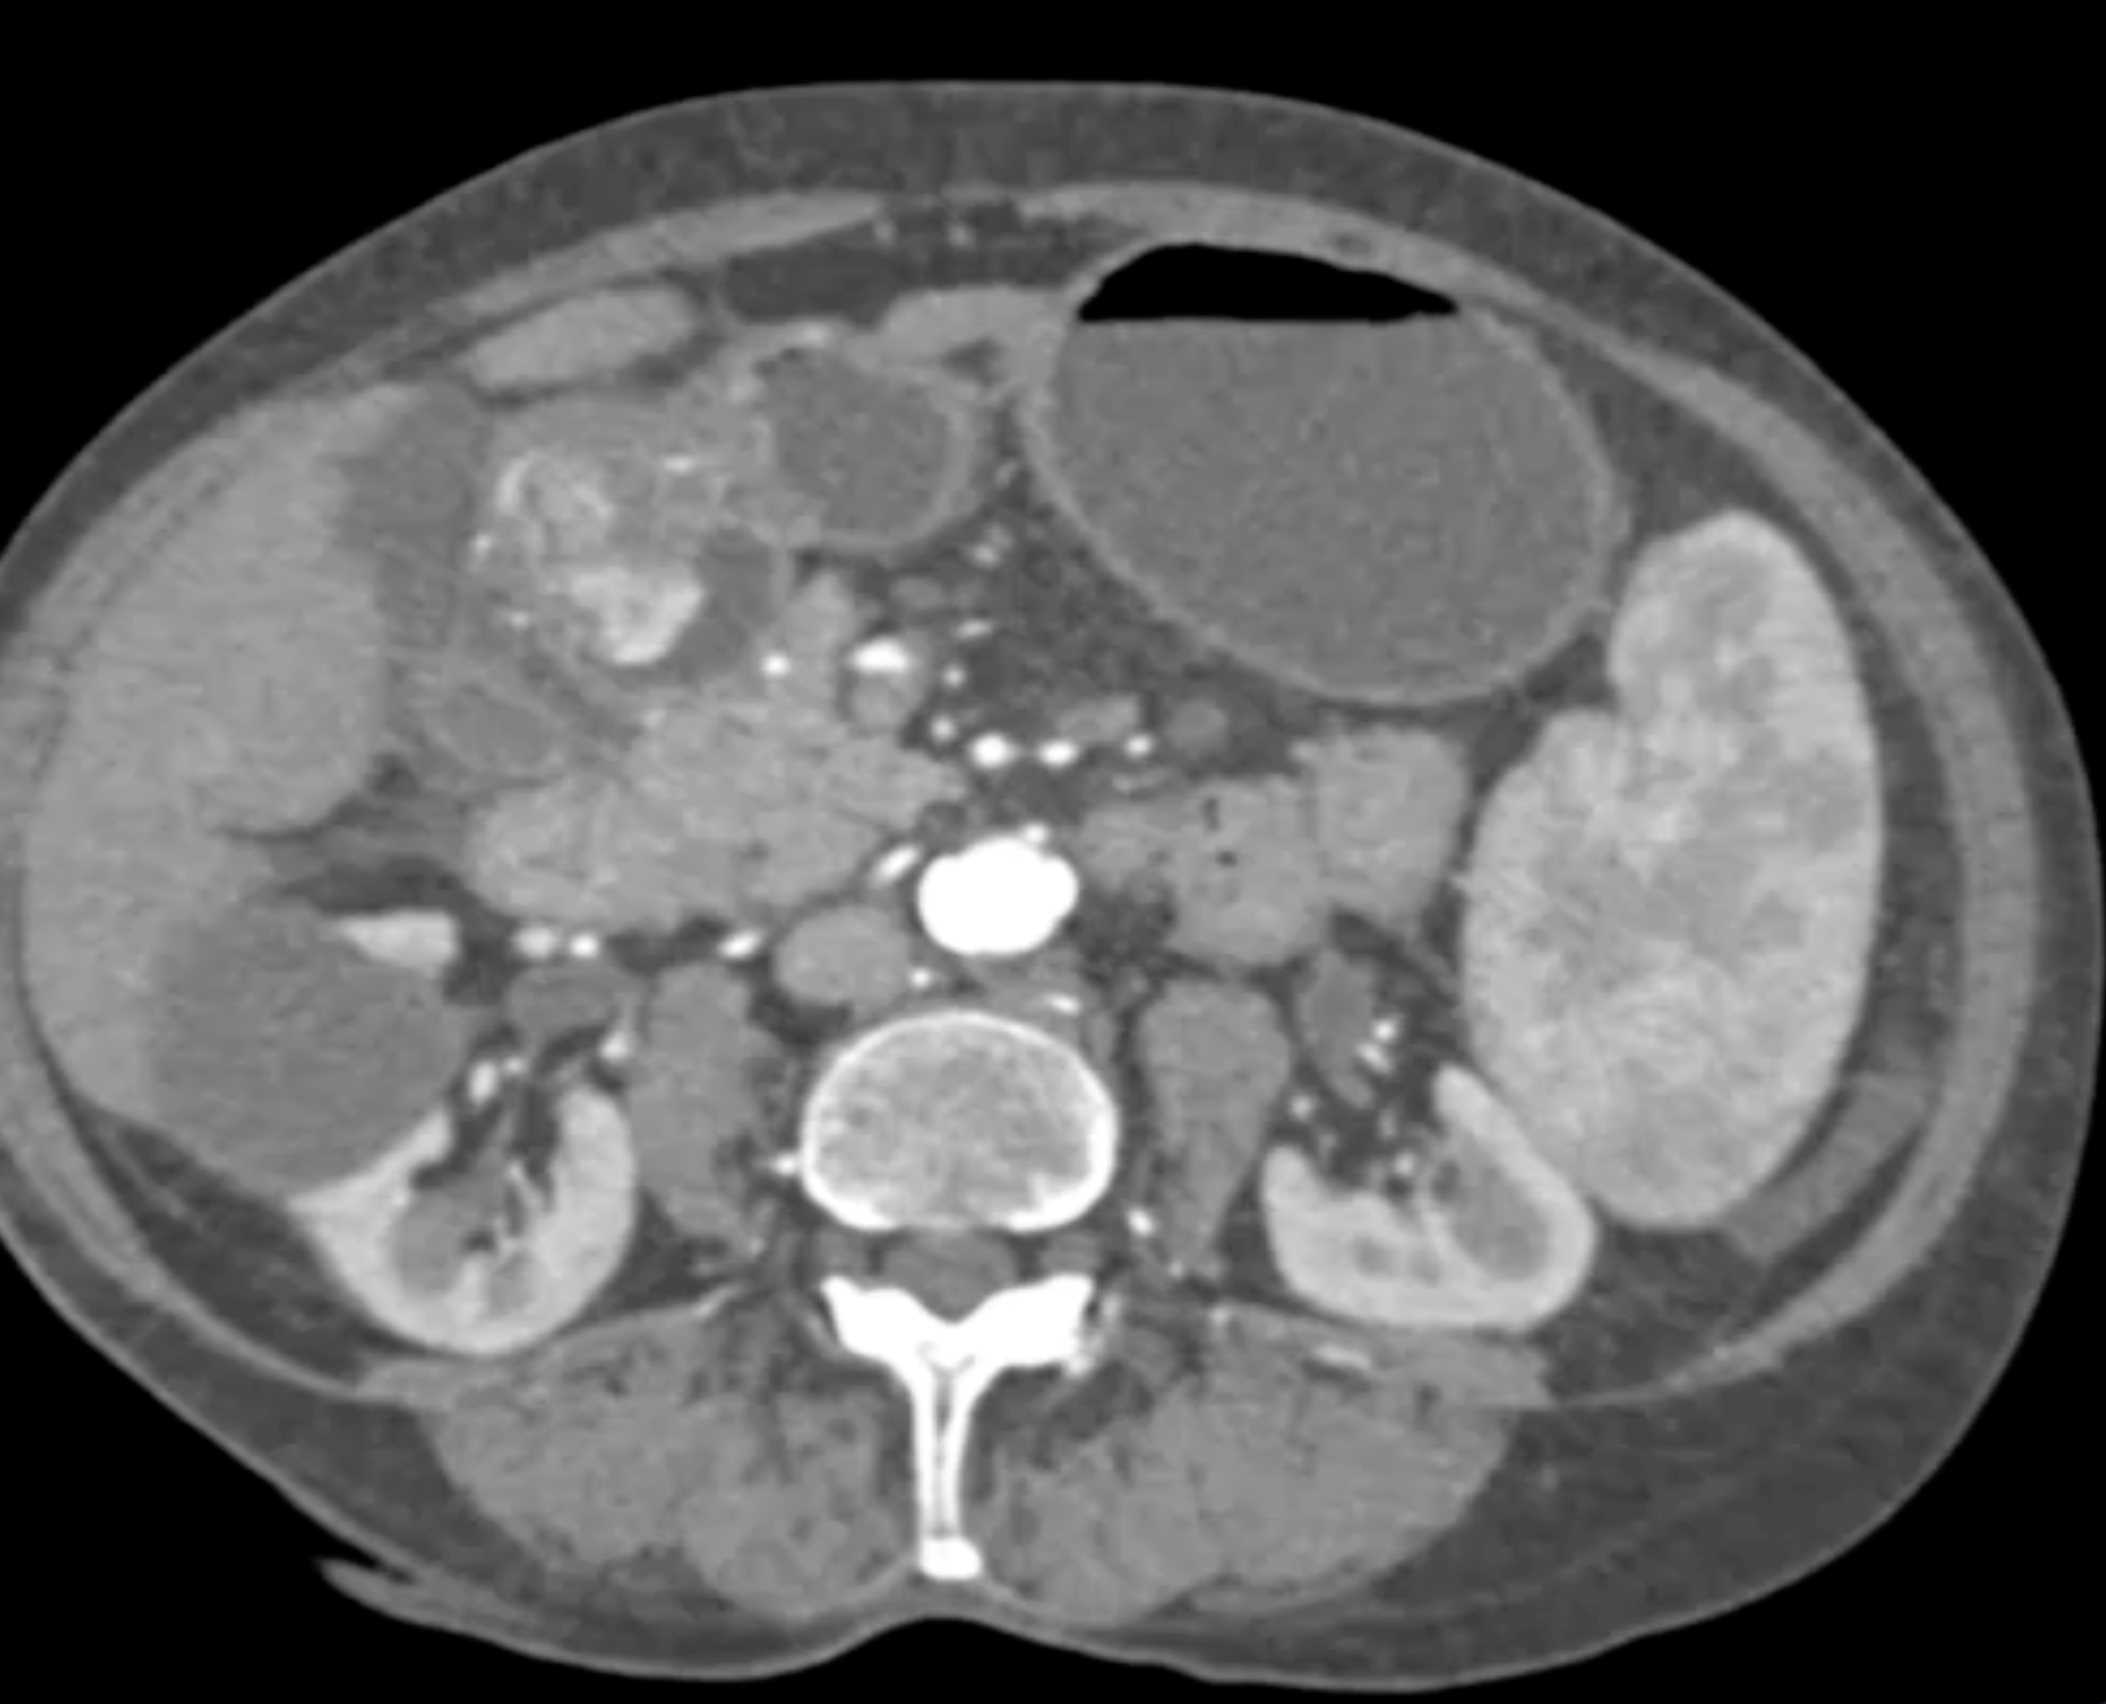

Watermelon Stomach (Gastric Antral Vascular Ectasis)